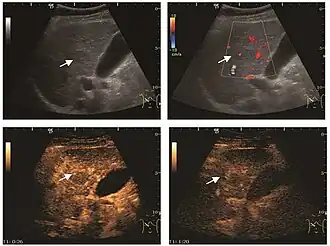

It is the most common liver tumor with a prevalence of 0.4 – 7.4%. It is generally asymptomatic but also can be associated with pain complaints or cytopenia and/or anemia when it is very bulky. It is unique or paucilocular. It can be associated with other types of benign liver tumors. Characteristic 2D ultrasound appearance is that of a very well defined lesion, with sizes of 2–3 cm or less, showing increased echogenity and, when located in contact with the diaphragm, a "mirror image" phenomenon can be seen. When palpating the liver with the transducer the hemangioma is compressible sending reverberations backwards. Doppler exploration reveals no circulatory signal due to very slow flow speed. CEUS investigation has real diagnosis value due to the typical behavior of progressive CA enhancement of the tumor from the periphery towards the center. The enhancement is slow, during several minutes, depending on the size of hemangioma and on the presence (or absence) of internal thrombosis. During late (sinusoidal) phase, if totally "filled" with CA, hemangioma appears isoechoic to the liver. Deviations from the above described behavior can occur in arterialized hemangiomas or those containing arterio-venous shunts. In these cases, differentiation from a malignant tumor is difficult and requires other imaging procedures, follow up and measurements of the tumor at short time intervals.[4]